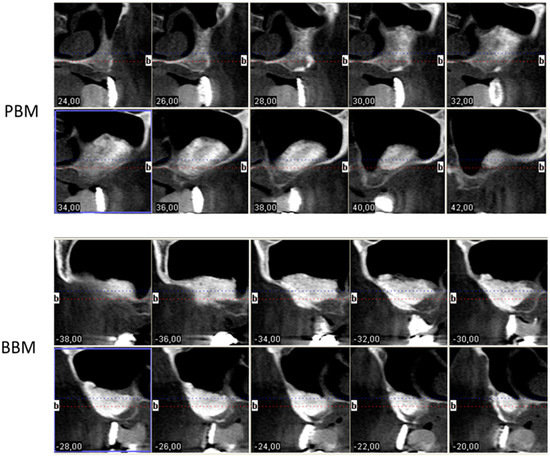

2.2. Radiological and Thermographic Results

4.2.4. Radiographic Thermal Imaging Analysis